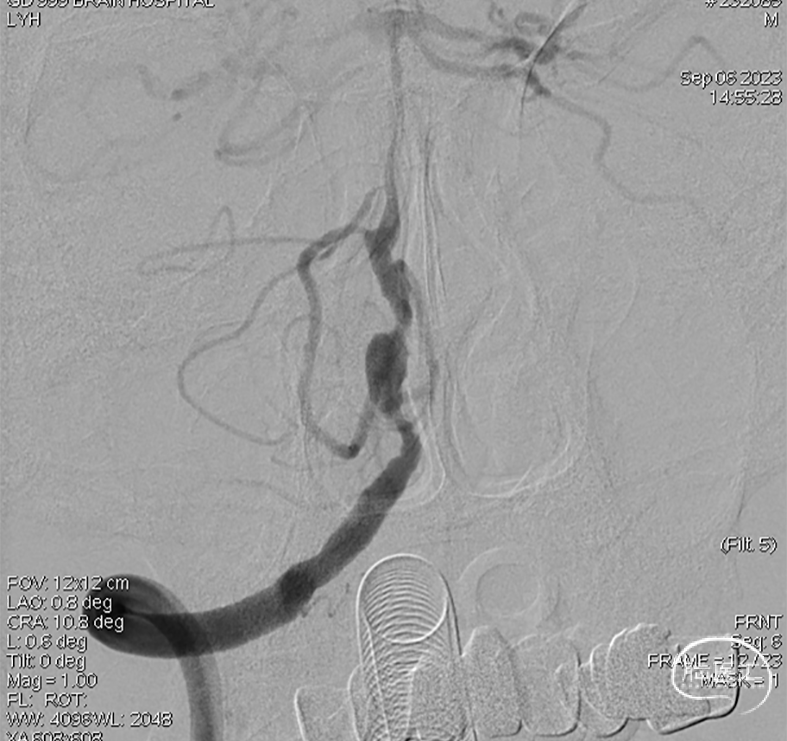

术后即刻DSA。

术后即刻稀释造影:“拉直”可见支架贴壁良好。